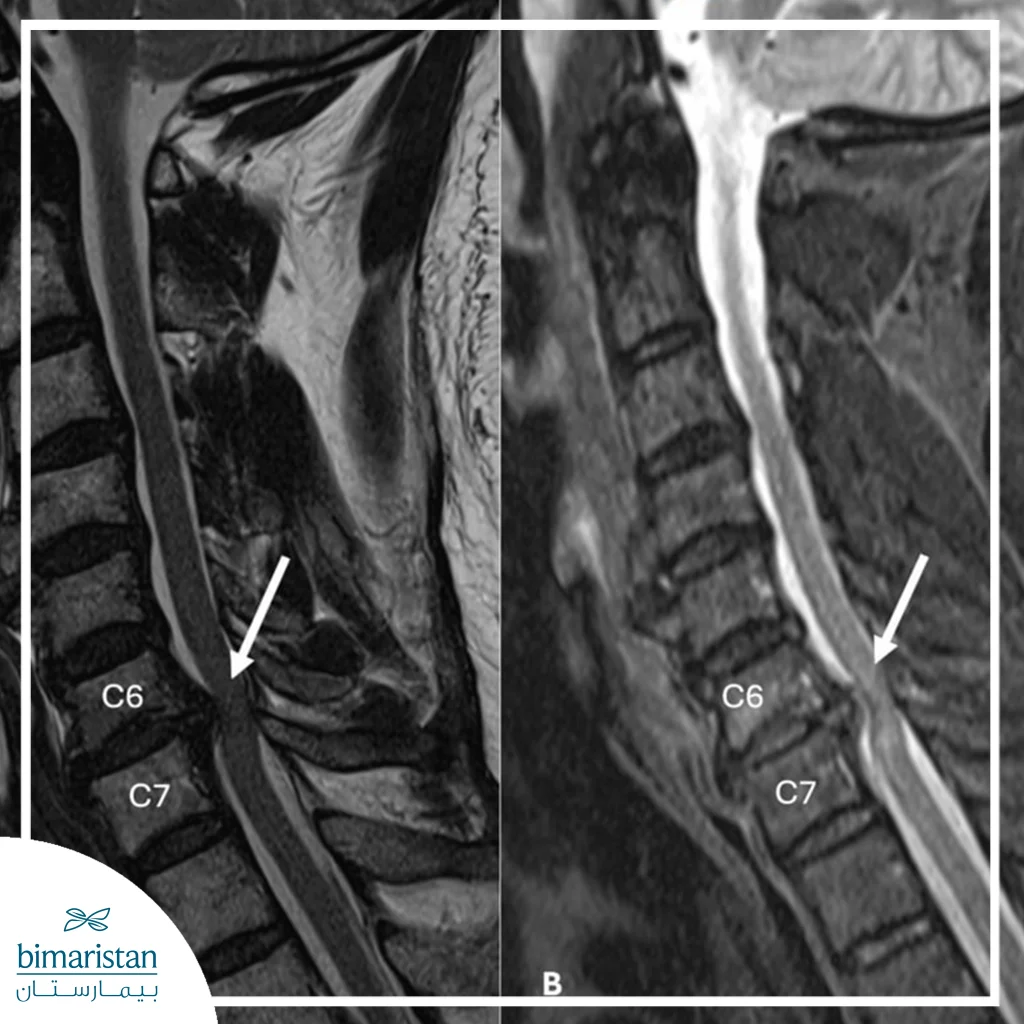

- Magnetic resonance imaging (MRI): This is the most accurate test for diagnosing a neck disc, as it clearly shows the slipped disc, its size, and the pressure it is exerting on the nerves or spinal cord.